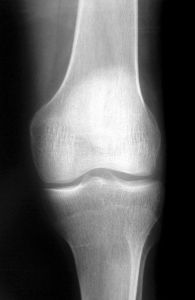

Reumatyzm zaczyna się od zwyrodnienia stawów to patologiczne zmiany chrząstki stawowej. Cierpiący na zwyrodnienia odczuwają sztywność stawów, która może trwać dłużej niż pół godziny (ta dolegliwość pojawia się z reguły rano). Ból nasila się podczas poruszania się. Zwyrodnieniowy ból w stawie biodrowym koncentruje się w pachwinie i z przodu (lub z boku) uda. Na skutek przykurczu w stawie może dojść do skrócenia kończyny.

W jaki sposób przeprowadzić stłuczenia leczenie? Stłuczony fragment ciała powinno się unieruchomić, trzeba robić zimne okłady, jakie złagodzą ból. Zwyrodnienia stawów są to patologiczne zmiany chrząstki stawowej. Chorujący na zwyrodnienia odczuwają sztywność stawów, jaka może trwać dłużej niż pół godziny (ta dolegliwość pojawia się z reguły rano). Ból nasila się podczas poruszania się. Zwyrodnieniowe bóle w stawie biodrowym skupiają się w pachwinie oraz z przodu (albo z boku) uda. Wskutek przykurczu w stawie może dochodzić do skrócenia jednej z kończyn.